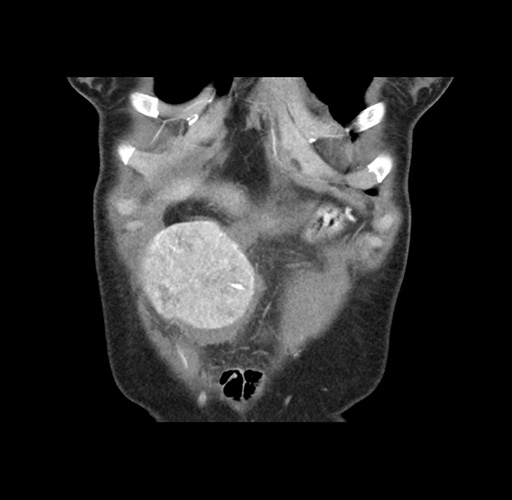

Imaging Analysis

Look through the patient's CT scan to identify any areas of concern for the necessary procedure.

Based on your CT findings, which issue(s) would give reason for "planned slowing down moment(s)" in this case?